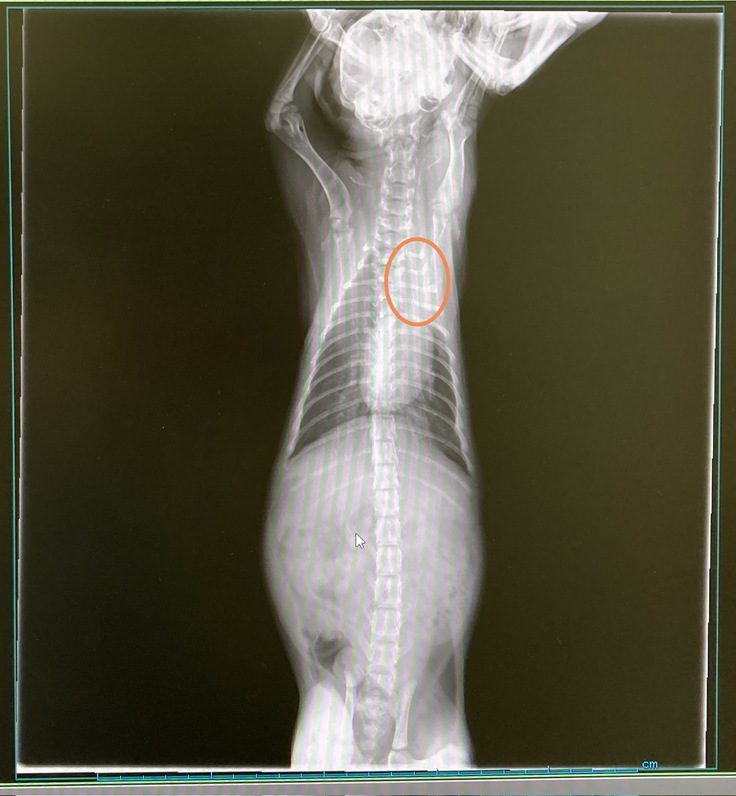

ヤマトは運動後の呼吸音が気になり相談したところ、左肺の上部が白く無気肺になっているかもしれないと言われ、気管支拡張薬を処方していただきました。ヤマトは来週も通院となります。肺炎自体は落ち着いているので、ワクチン1回目をナイトと同時に打ってきました。